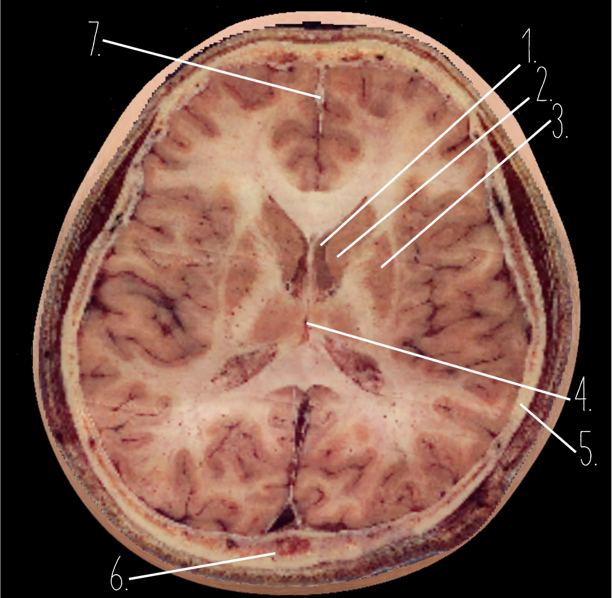

Brain Cross Sectional

1

Frontal Bone

2

Frontal Lobe

3?

Falx Cerebri

4?

Gray Matter

5?

White Matter

6?

Sulcus

7?

Gyrus